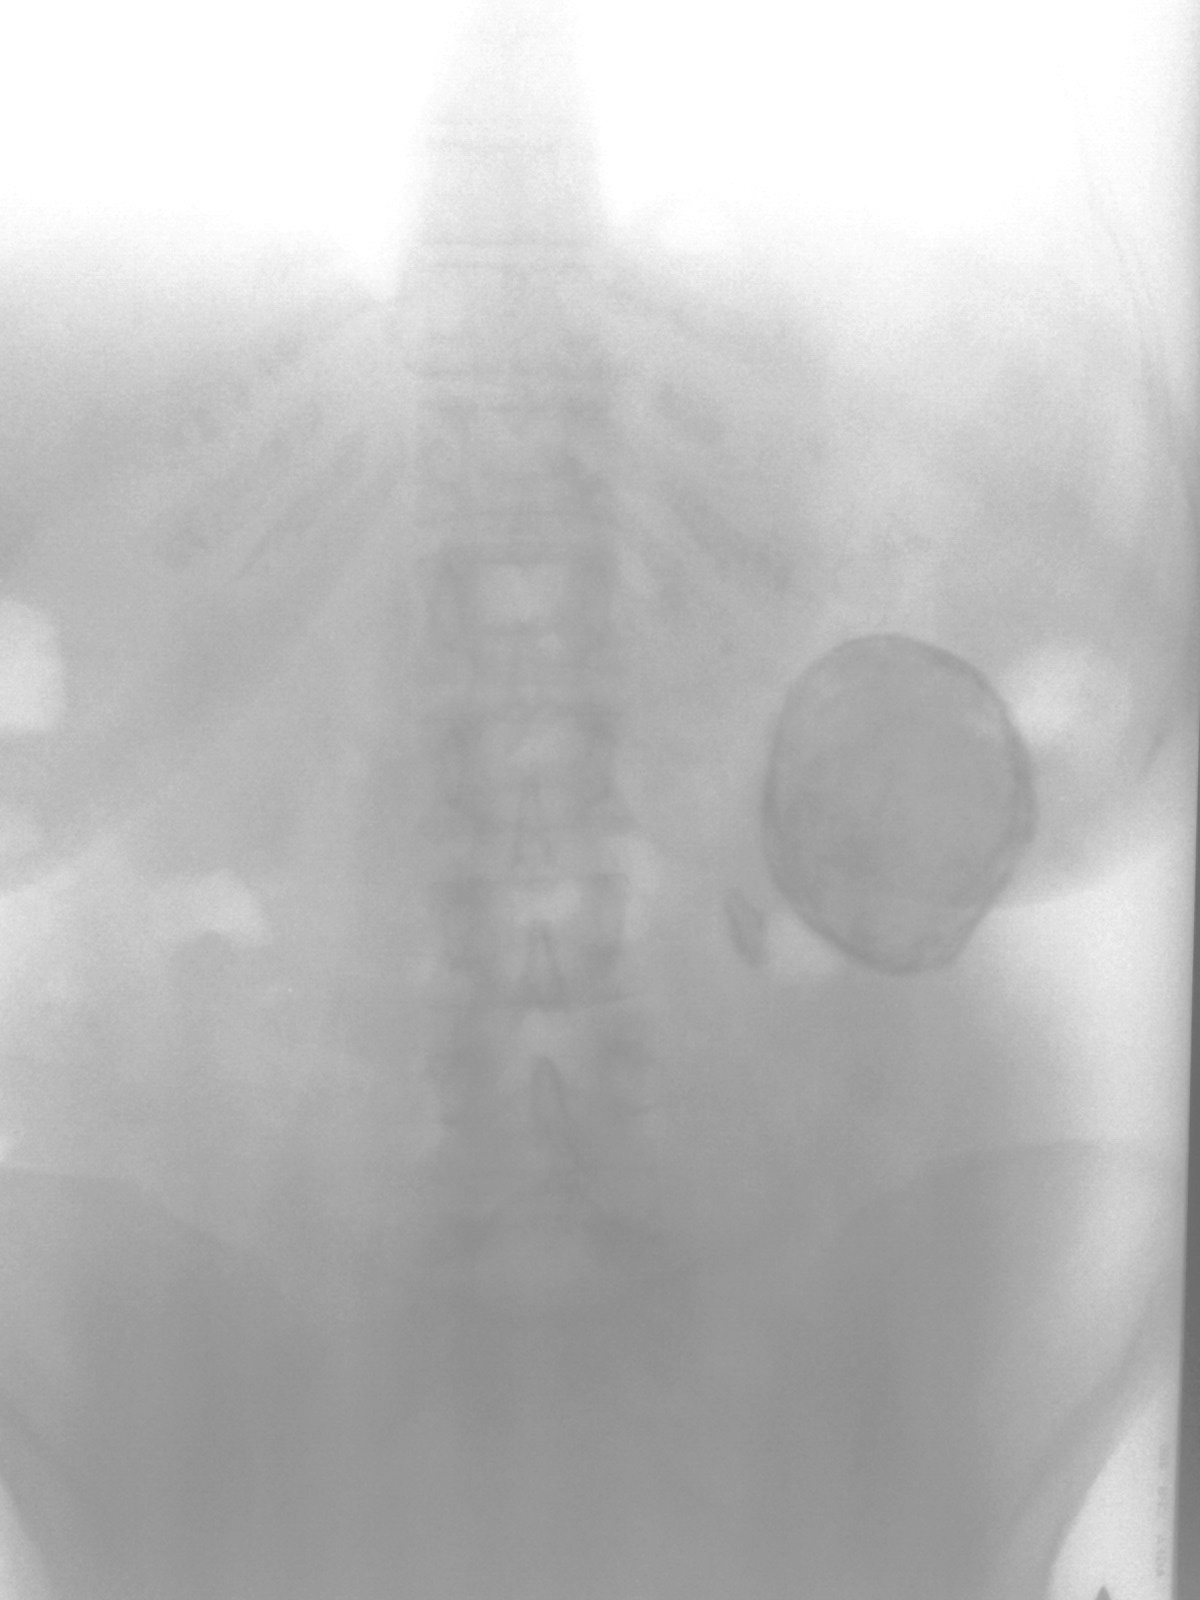

Во время прохождения специализации по рентгенологии встретился данный случай. Женщина 60 лет направлена с д-зом перитонит? перфорация?

Снимки заснял на то что было под рукой =(

Что это обызвествление почки маловероятно. Что это огромный конкремент или киста более вероятно.Доже гигантсткий конкремент более вероятен. Более мелкий конкремент, формы, приближающейся к треугольной располагается, по всей видимости, в лоханочно-мочетониковом сегменте.

Что-то плоховато видна паренхима самой левой почки, точнее вообще не видна.

Украинские коллеги по данным УЗИ пишут о кистозной многокамерной дегенерации левой почки с массивными обызвествлениями. Скорее всего так оно и есть.

Обработал, представленные Вами изображения. Конечно, мелкий конкремент располагается в лоханочно-мочеточниковом сегменте. Тень значительных размеров - или конкремент, или кистозное образование, не исключается в том числе, и эхинококковая киста.

Обязательно надо сделать внутривенную урографию. Насчет лоханочно-мочеточникового сегмента - как-то недоказательно, а насчет "большого конкремента" - склоняюсь к эхонококку селезенки... Держите нас в курсе, пожалуйста.